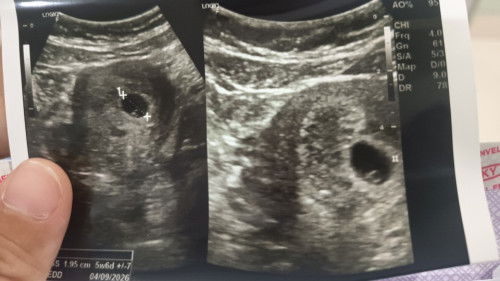

USG 5w6d kantung yolk sac tidak bulat sempurna

USG 5w6d dibilang kantung yolk sac tidak bulat sempurna. Jd 50:50 dokter ga bs bilang sehat jg. Msh nunggu kontrol seminggu lg tp penasaran. Ada yg punya pengalaman yg sama?